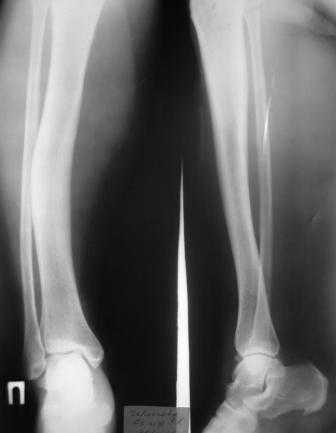

Фиброзная дисплазия?

Пациентка Ч. дата рождения 28.02.1962. Болеет на протяжении 3 лет, появились боли в левой голени, отеки голени, стопы. Обследования не проходила, лечения не получала.

Заключение гистолога: присланы скудные биоптаты из опухоли левой б/берцовой кости в виде мелких фрагментов размерами 0.2 х 0.5 см, с наличием костных фрагментов губчатого вида и мягкотканных кусочков. При исследовании: иррегулярные костные балки обычной архитектоники без атипии остеоида, лежат изолированно друг от друга, между ними зрелая клеточно-волокнистая фиброзная ткань. В прилежащей клетчатке очаги отложения солей кальция, мелкоочаговые кровоизлияния. Более всего можно думать о фиброзной дисплазии.

У нас обследование: гаммасцинтиграфия – очаги скопления препарата в левой б/берцовой кости, 8 ребре слева. Данных за б-нь Педжета нет.

- правая голень – варусная деформация диафиза б/берцовой кости.

После обсуждения пациентки к единому мнению по тактике лечения данной пациентки прийти не удалось. Может быть кто-то сможет поделиться своим опытом или мыслями по данному поводу?